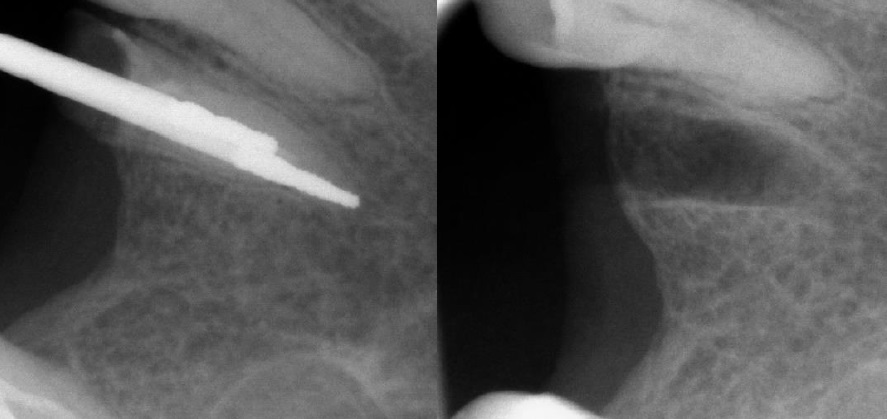

Для зубов с одним корнем фреза направляется вдоль оси зуба. В случае нижних многокорневых зубов разрез проводится между медиальным и дистальным корнями параллельно оси зуба. Для верхних моляров траектория проходит вдоль линии трифуркации корней, также параллельно оси зуба. Такой подход обеспечивает высокую точность и минимальную травматичность вмешательства (рис. 3, 4).

Рис. 3. Клиническая ситуация до удаления зуба (справа) и после применения фрез через навигационный шаблон (слева)

Рис. 4. Рентгенография во время применения фрез для разделения корня на фрагменты (слева) и «пустая» лунка после удаления корня (справа)

Фрезы прошли строго по оси зуба, обозначив необходимую глубину препарирования и вектор дальнейших движений фрезой.

На рентгенографии во время применения фрез отмечается точное расположение кончика фрезы на верхушке корня зубы, без дополнительной травмы, окружающих тканей.